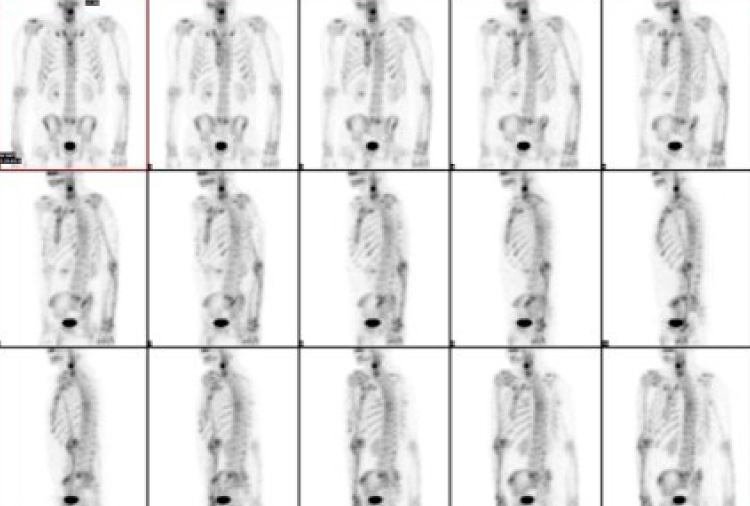

核医学検査

核医学検査とは

当院の特色